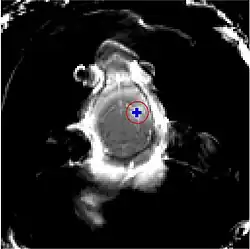

Les ultrasons peuvent être focalisés sur n'importe quel domaine du cerveau. C'est ainsi que l'on peut ouvrir la barrière hémato-encéphalique sélectivement sur des régions délimitées du cerveau. Les médicaments administrés pénétreront alors sur la zone ainsi ciblée[138]. On peut suivre le ciblage des zones par une IRM simultanée : il suffit d'administrer un produit de contraste IRM, comme du gadolinium convenablement chélaté, qui pénètre dans le cerveau à travers les parties de la barrière hémato-encéphalique ouvertes. Ces parties deviennent alors visibles en IRM. Les produits de contraste ne sont pas en mesure de franchir la barrière aux endroits où elle n'est pas ouverte.

Sur le modèle animal de la souris, on a utilisé des ultrasons focalisés dans le domaine de 0,5 à 2 MHz[139], avec de brèves impulsions de l'ordre de la milliseconde, répétées à intervalles de 1 s, pour une durée totale inférieure à une minute[140]. La fréquence optimale se situe au-dessous de 1 MHz[141]. La puissance acoustique instantanée est inférieure au watt, et donc la puissance moyenne de l'ordre du mW. Les microbulles utilisées sont en général des microbulles autorisées pour l'échocardiographie de contraste. Elles ont typiquement un diamètre de 3 à 5,5 μm, et sont composées typiquement d'albumine humaine, remplie d'octafluoropropane ou de gaz lourd semblable[142].